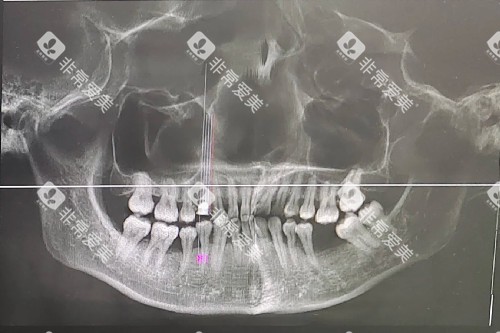

"可不是吓唬人!"北京协和医院口腔科李明阳医师敲着牙片模型,"我们跟踪了200例缺牙患者,发现超过3个月不修复的,牙槽骨高度每年减少2-4mm,宽度萎缩更明显。"他翻出一张CT片:缺牙区原本饱满的骨组织,6个月后竟凹陷出明显的"坑洞"。

更惊人的是萎缩速度——初期每月0.1mm,6个月后加速到每月0.2mm。"就像水土流失,越不管它越严峻。"李医师指着模型上的刻度线,"等骨量不够了,种牙得先花几万块做骨增量手术,何必呢?"